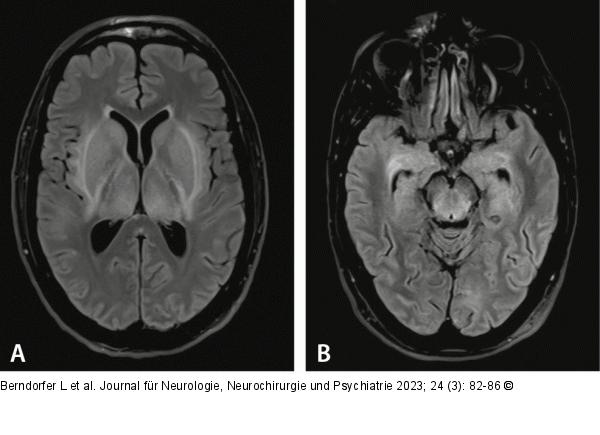

Abbildung 1A-B: Hirnödem cMRT Aufnahmetag: T2 dark fluid axial; T2-Hyperintensität im Bereich der Basalganglien, Thalami und des Mittelhirns als Ausdruck des vasogenen Ödems |

cMRT Aufnahmetag: T2 dark fluid axial; T2-Hyperintensität im Bereich der Basalganglien, Thalami und des Mittelhirns als Ausdruck des vasogenen Ödems |